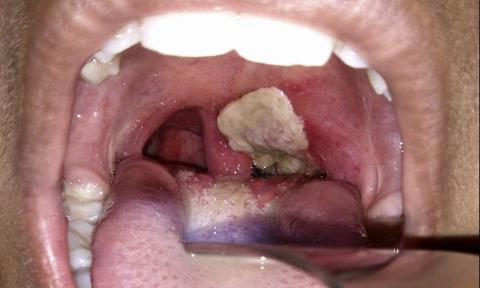

The Health Ministry has confirmed three more diphtheria cases in Johor as of yesterday.

It was reported earlier that five children suspected to be diphtheria positive were being treated at the pediatric isolation ward of the Sultanah Aminah Hospital in Johor Bahru.

In a statement today, Health director-general Dr Noor Hisham Abdullah said the cases involved a four-year-old boy and girl, as well as a 15-year-old girl, who all lived in the same house as the two-year-old believed to have died from diphtheria on Feb 21.

The four-year-old girl who tested positive for the disease was the sister of the deceased toddler.

“All three children were treated for the disease and are in a stable condition, and one has since been allowed to return home,” he said.